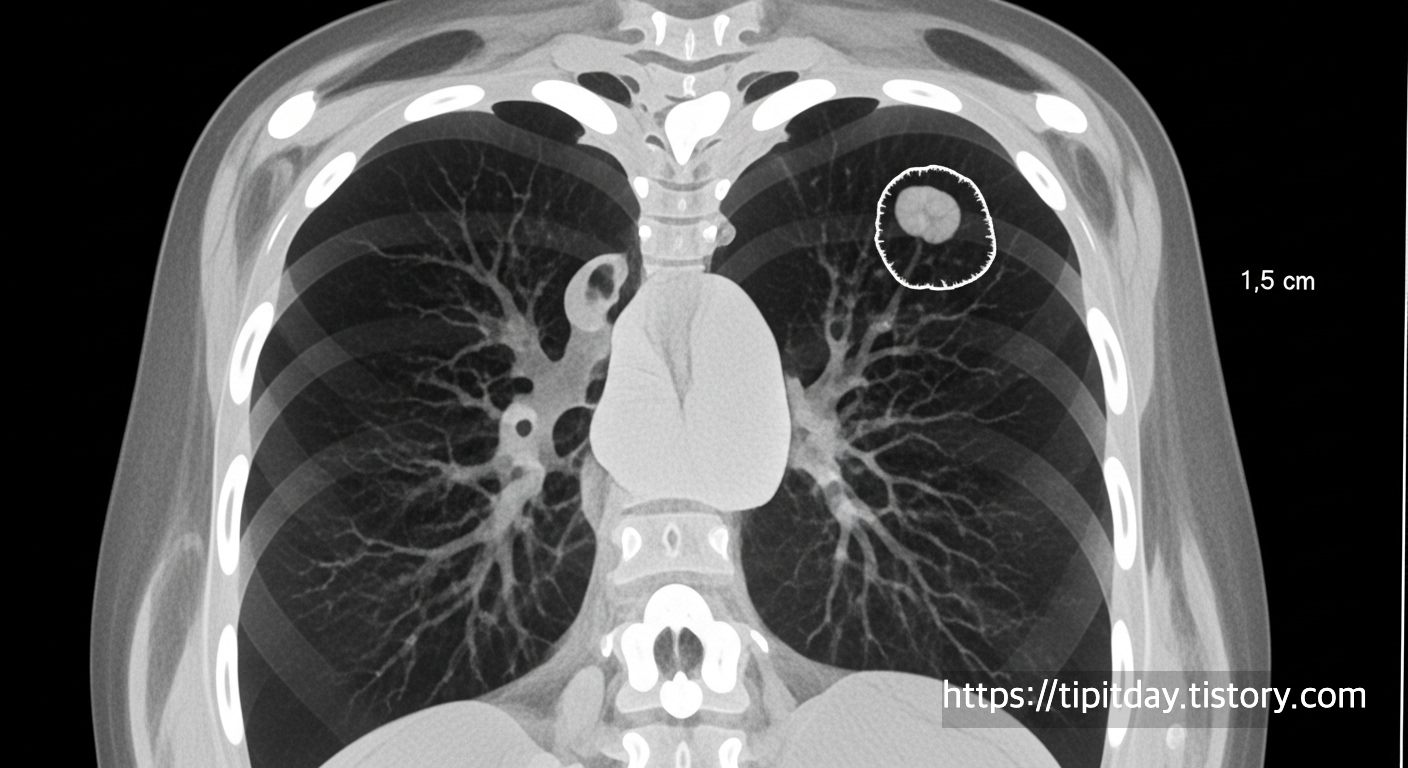

폐결절은 폐 내부에 생긴 지름 3cm 이하의 고립된 음영(덩어리)을 말합니다.

CT나 X-ray 검사에서 작은 동그라미처럼 보이며, 보통은 증상이 없습니다.

모양, 경계, 음영 정도에 따라 '고형 결절', '유리음영(GGO)', '부분 고형' 등으로 분류됩니다.